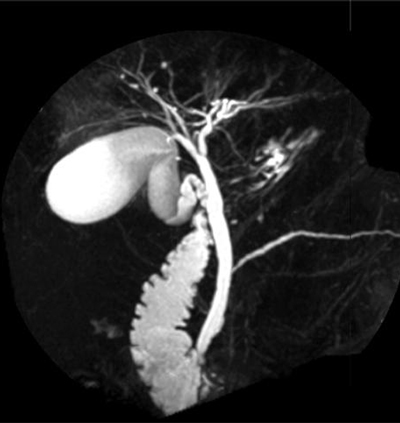

Manyetik Rezonans Kolanjiyopankreatografi (MRCP)

Girişim gerektirmeyen bu tanı yöntemi, safra kanallarının bilgisayar görüntülerini üretmek için MRI teknolojisini (mıknatıslar ve radyo dalgaları) kullanarak radyolojide gerçekleştirilir. Resimleri geliştirmek için karın cildinden önce kontrast boya enjekte edilir. Hastaların endoskopi hazırlığı yapmaları gerekmez ve sedasyona maruz kalmazlar. MRCP, özellikle başarısız olmuş ya da ERCP için iyi bir aday olmayan, Endoskopik bir prosedürden geçmek istemeyen hastalarda ve pankreatik kanal veya safra kanalı bozukluğu riski düşük olan bireylerde kullanılmaktadır. ERCP kolanoskopiyle tedavi seçeneklerine izin verirken, MRCP sadece bir tanı aracıdır.